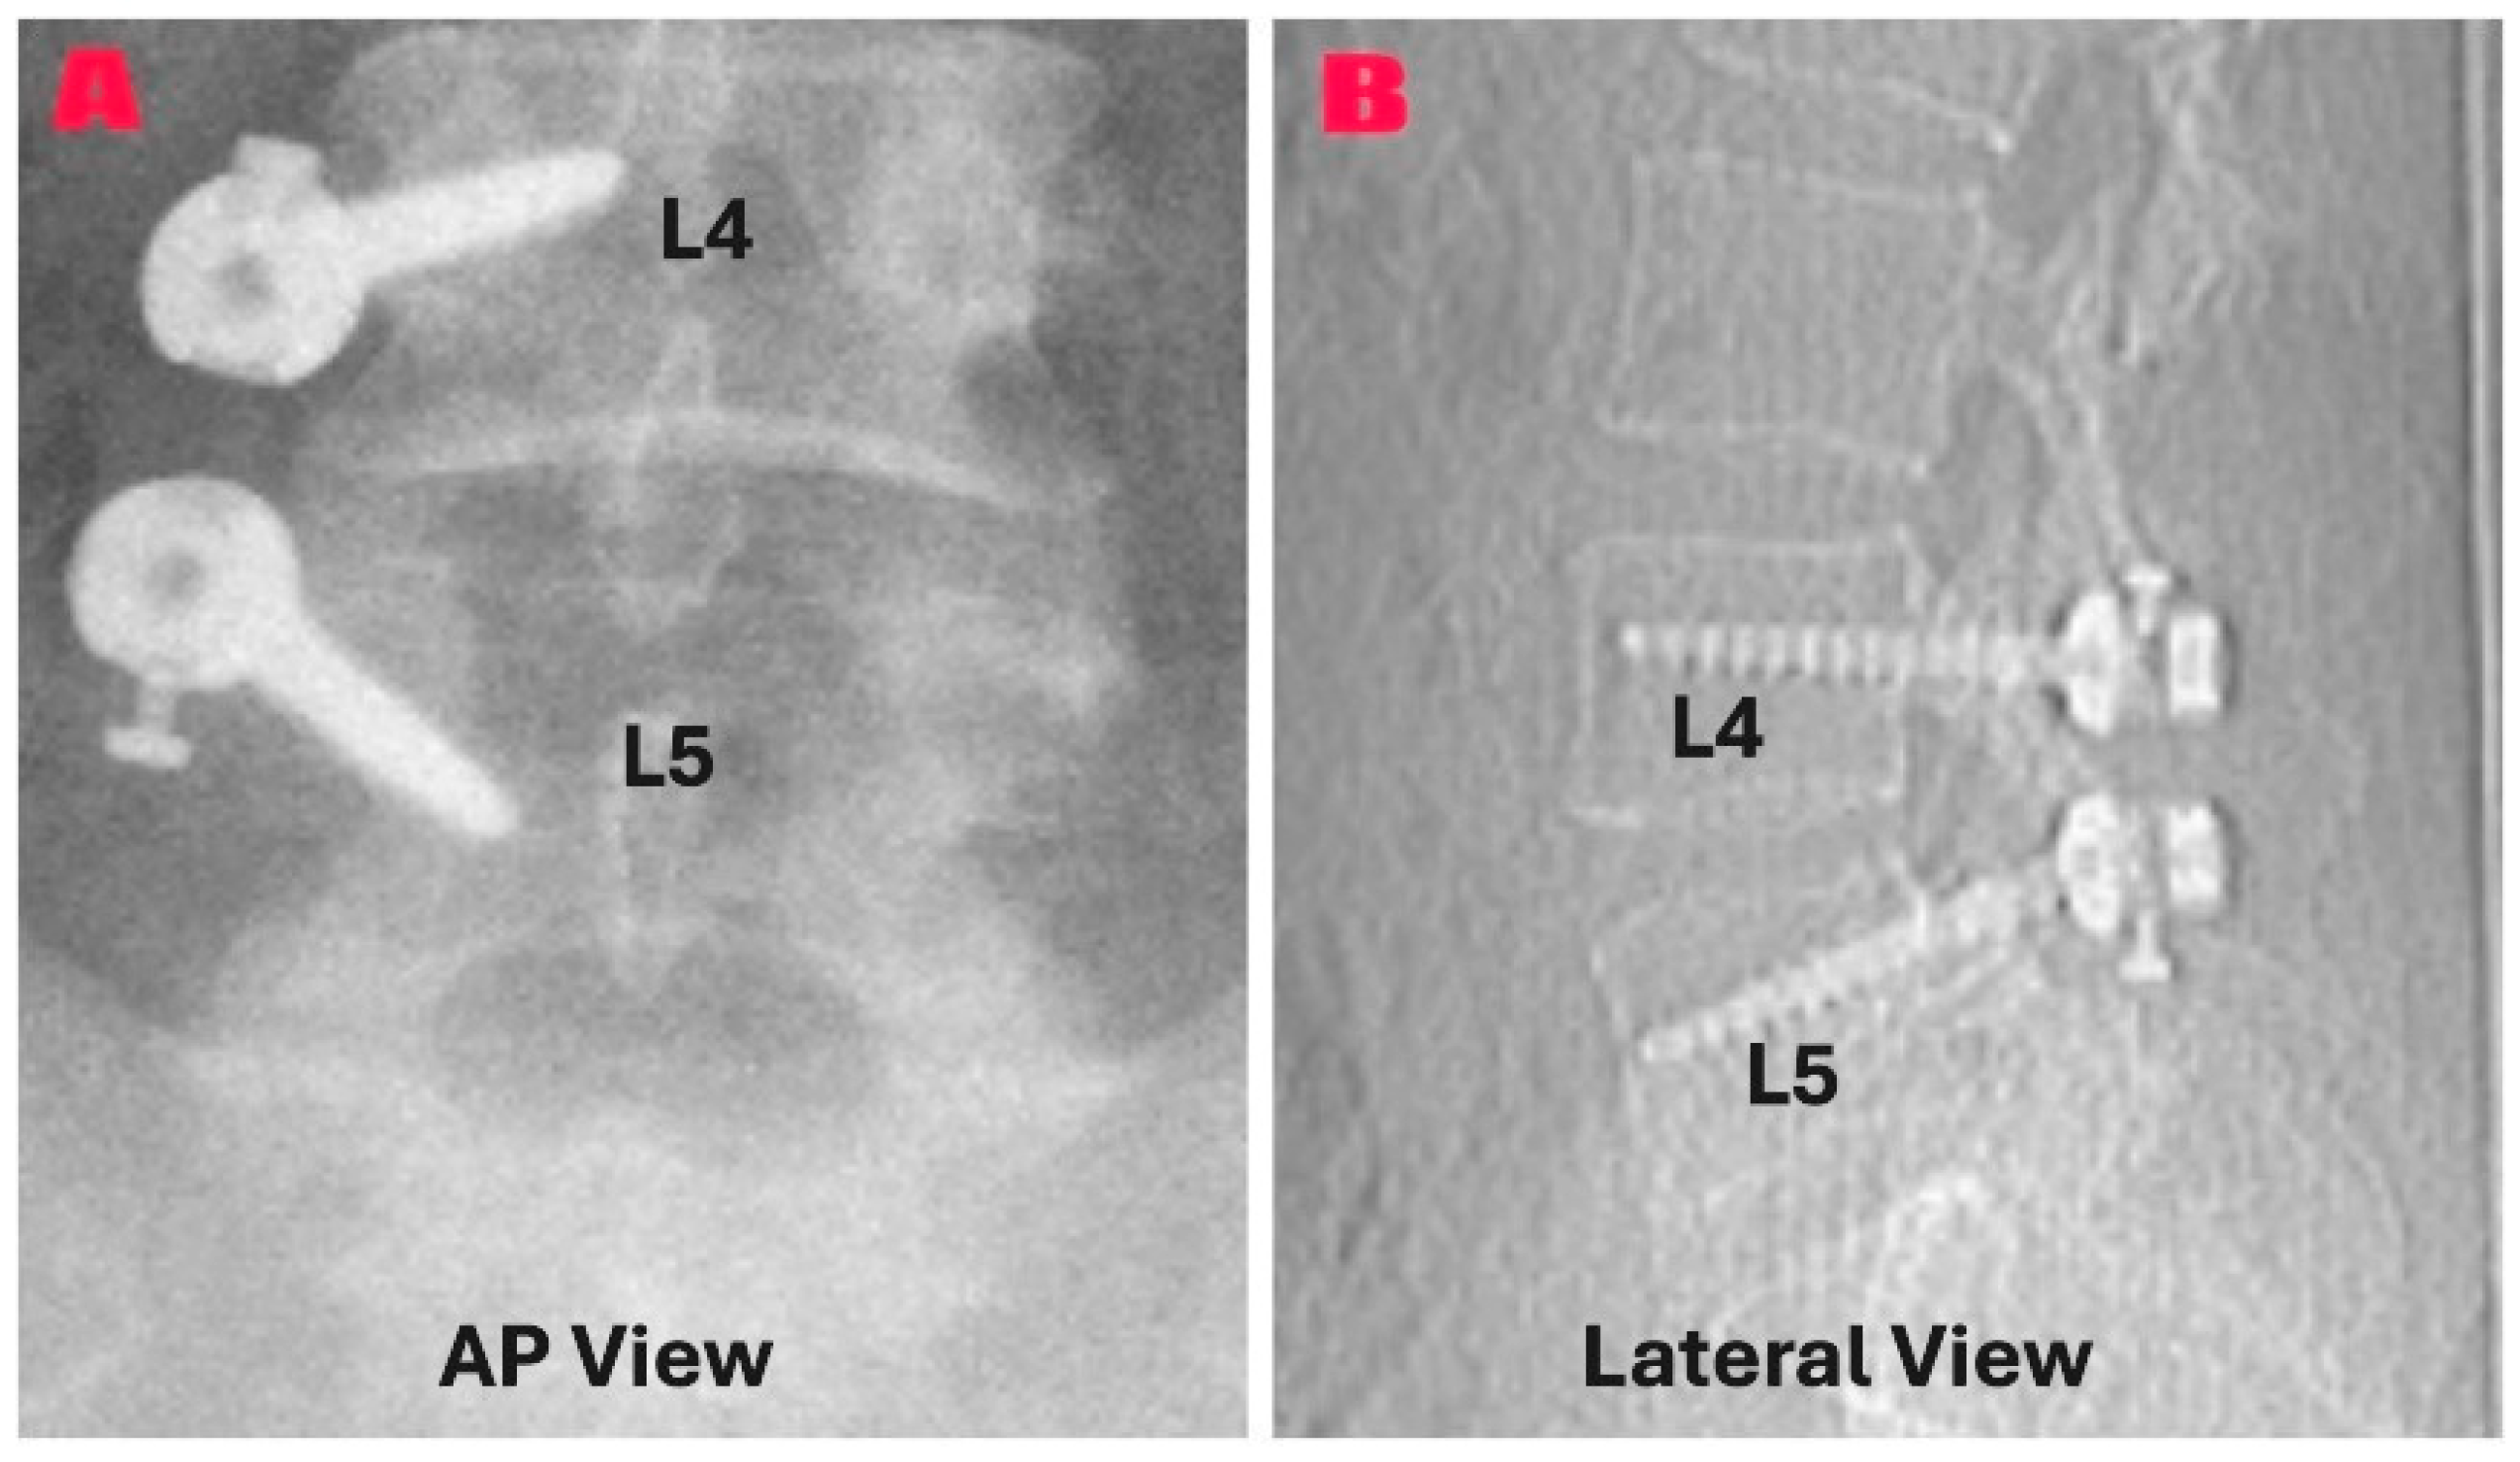

In the group composed of patients who underwent excision with unilateral instrumentation (n = 15), wider exposure was provided on the cyst side. Following the pedicle screws were placed and verified by fluoroscopy, cyst excision was performed using the same technique. After hemostasis, pedicle screws were connected with a PEEK rod. Facet joint mobility was assessed before and after instrumentation. Closure was performed in anatomical layers. Figure 3 shows a representative postoperative radiograph (A) and CT scan (B) from the instrumentation group, demonstrating pedicle screw placement in anteroposterior (A) and lateral (B) views.

Figure 3. Postoperative imaging that shows unilateral PEEK rod instrumentation at the L4–L5 level following a synovial cyst excision. (A) An anteroposterior radiograph showing the proper placement of unilateral pedicle screws in the L4 and L5 vertebrae (B). The CT scan showing the PEEK rod and the pedicle screws applied unilaterally and properly reveals that the segmental alignment has been maintained.